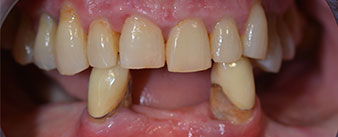

Die notwendige parodontologische Behandlung und Extraktion im Oberkiefer sollte zu einem späteren Zeitpunkt erfolgen, da die Patientin Lehrerin ist und zu dem Zeitpunkt mit Abiturprüfungen beschäftigt war. Sie konnte weder essen noch adäquat sprechen, da die Interimsprothese sehr häufig und bei der kleinsten Belastung brach.

Nach der Aufklärung über die verschiedenen Möglichkeiten der Versorgung entschied sich die Patientin für eine Extraktion der Restbezahnung im Unterkiefer, eine Sofortimplantation und Versorgung mit der sogenannten Fast & Fixed-Methode (bredent medical). Hierbei wird der provisorische festsitzende Zahnersatz bereits am OP-Tag auf vier Implantaten verschraubt. Das Ziel war, die Patientin am Freitag zu operieren, sodass sie am Montag darauf an den mündlichen Abiturprüfungen teilnehmen konnte.